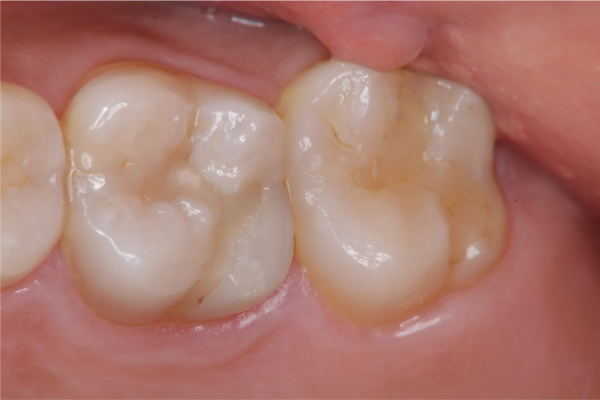

治療前,二次蛀牙

蛀牙未到牙髓